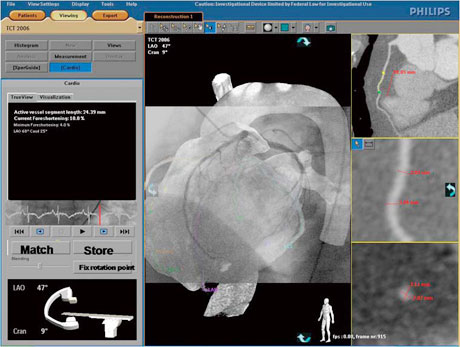

心臓CTの進歩は目覚ましく,現在では多くの施設で活用されている。心臓CTでは,高精細な3D画像が生成され,これらは複雑なPCI時に多用され始めている。フィリップスでは,心臓CTデータを利用し最適なアプローチアングルをシミュレートして,目的のワーキングアングルへのオートポジションを実現する“CT TrueView”を開発した。このアプリケーションソフトウェア上で術者は,選択病変部の最適なアングルを選択することができる。また,Optimal View Map機能により,臨床角度を装置側が自動計算し提示する(図3)。

図3 CT TrueView